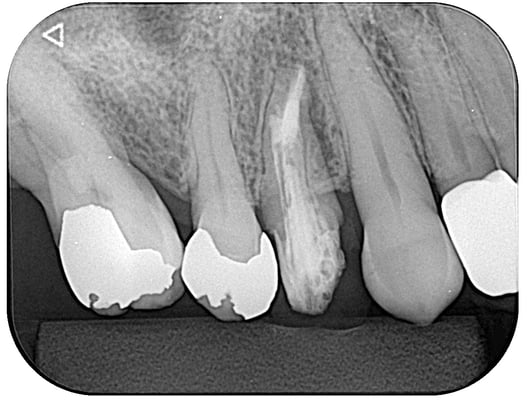

右上7番

根管内には、3本の破折ファイルの残存。それ以外は、多量の軟化象牙質(一部は髄床底穿孔)。根尖病巣の存在。対合歯とのクリアランス少なく、保存するにも補綴するには無理か?と思われましたが、約1年。月に1度。当院から片道2時間半、かけて通っていただき、無事に補綴に至りました。

これから矯正治療になりますので、まだまだ長い道のりです。